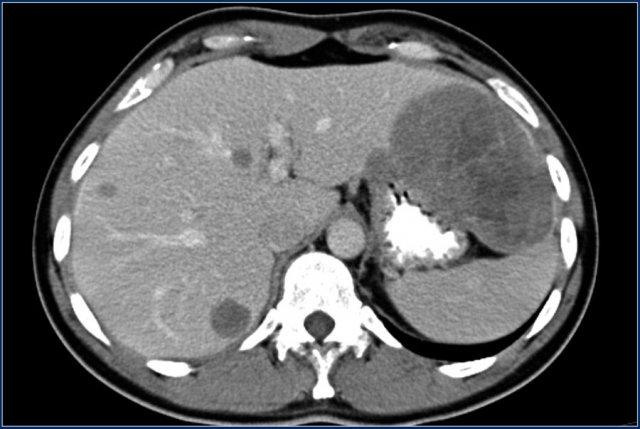

U carcinoid có vôi hóa và phản ứng xơ hóa desmoplastic. Tắc ruột non do thành phần trong lòng ruột của u carcinoid. Lưu ý tổn thương di căn gan nhỏ (mũi tên).

Di căn gan thường có tính chất tăng sinh mạch và có thể có hoại tử trung tâm.

Bốn năm sau lần chụp CT ban đầu, ghi nhận nhiều tổn thương di căn gan.

Lưu ý kiểu ngấm thuốc tăng sinh mạch trong thì động mạch muộn.